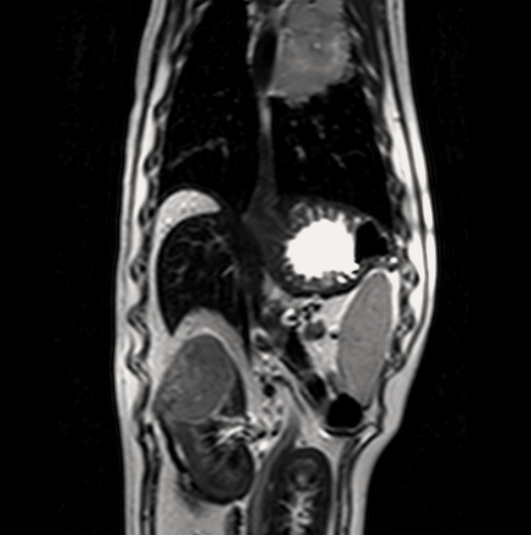

МРТ исследования проводятся на аппарате высокого качества Phillips Intera с напряженностью магнитного поля 1,5 Тесла. Позволяет максимально точно визуализировать анатомические структуры одинаково хорошо животному от 200г до 200кг

- Проведение мрт животному

- Подозрении на новообразование, когда установить диагноз другими методами невозможно.